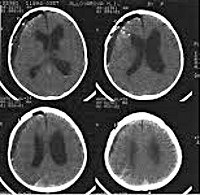

CT scan of the brain of a child.

КТ головного мозга ребенка. Высокочувствительный метод лучевой диагностики, позволяющий получать серийные срезы головного мозга в горизонтальной, сагиттальной и фронтальной плоскостях. В детской неврологии КТ головного мозга проводится с врожденными аномалиями развития мозга (микроцефалия, гидрофобия ), Внутричерепными гематомами, опухолями и поражениями головного мозга, менингитом, энцефалитом, а также для контроля лечения этих и других заболеваний. КТ головного мозга может привести детей с головными болями, судорогами, эпизодами потери сознания. Для изучения состояния сосудистого русла выполняется компьютерная томография головного мозга.